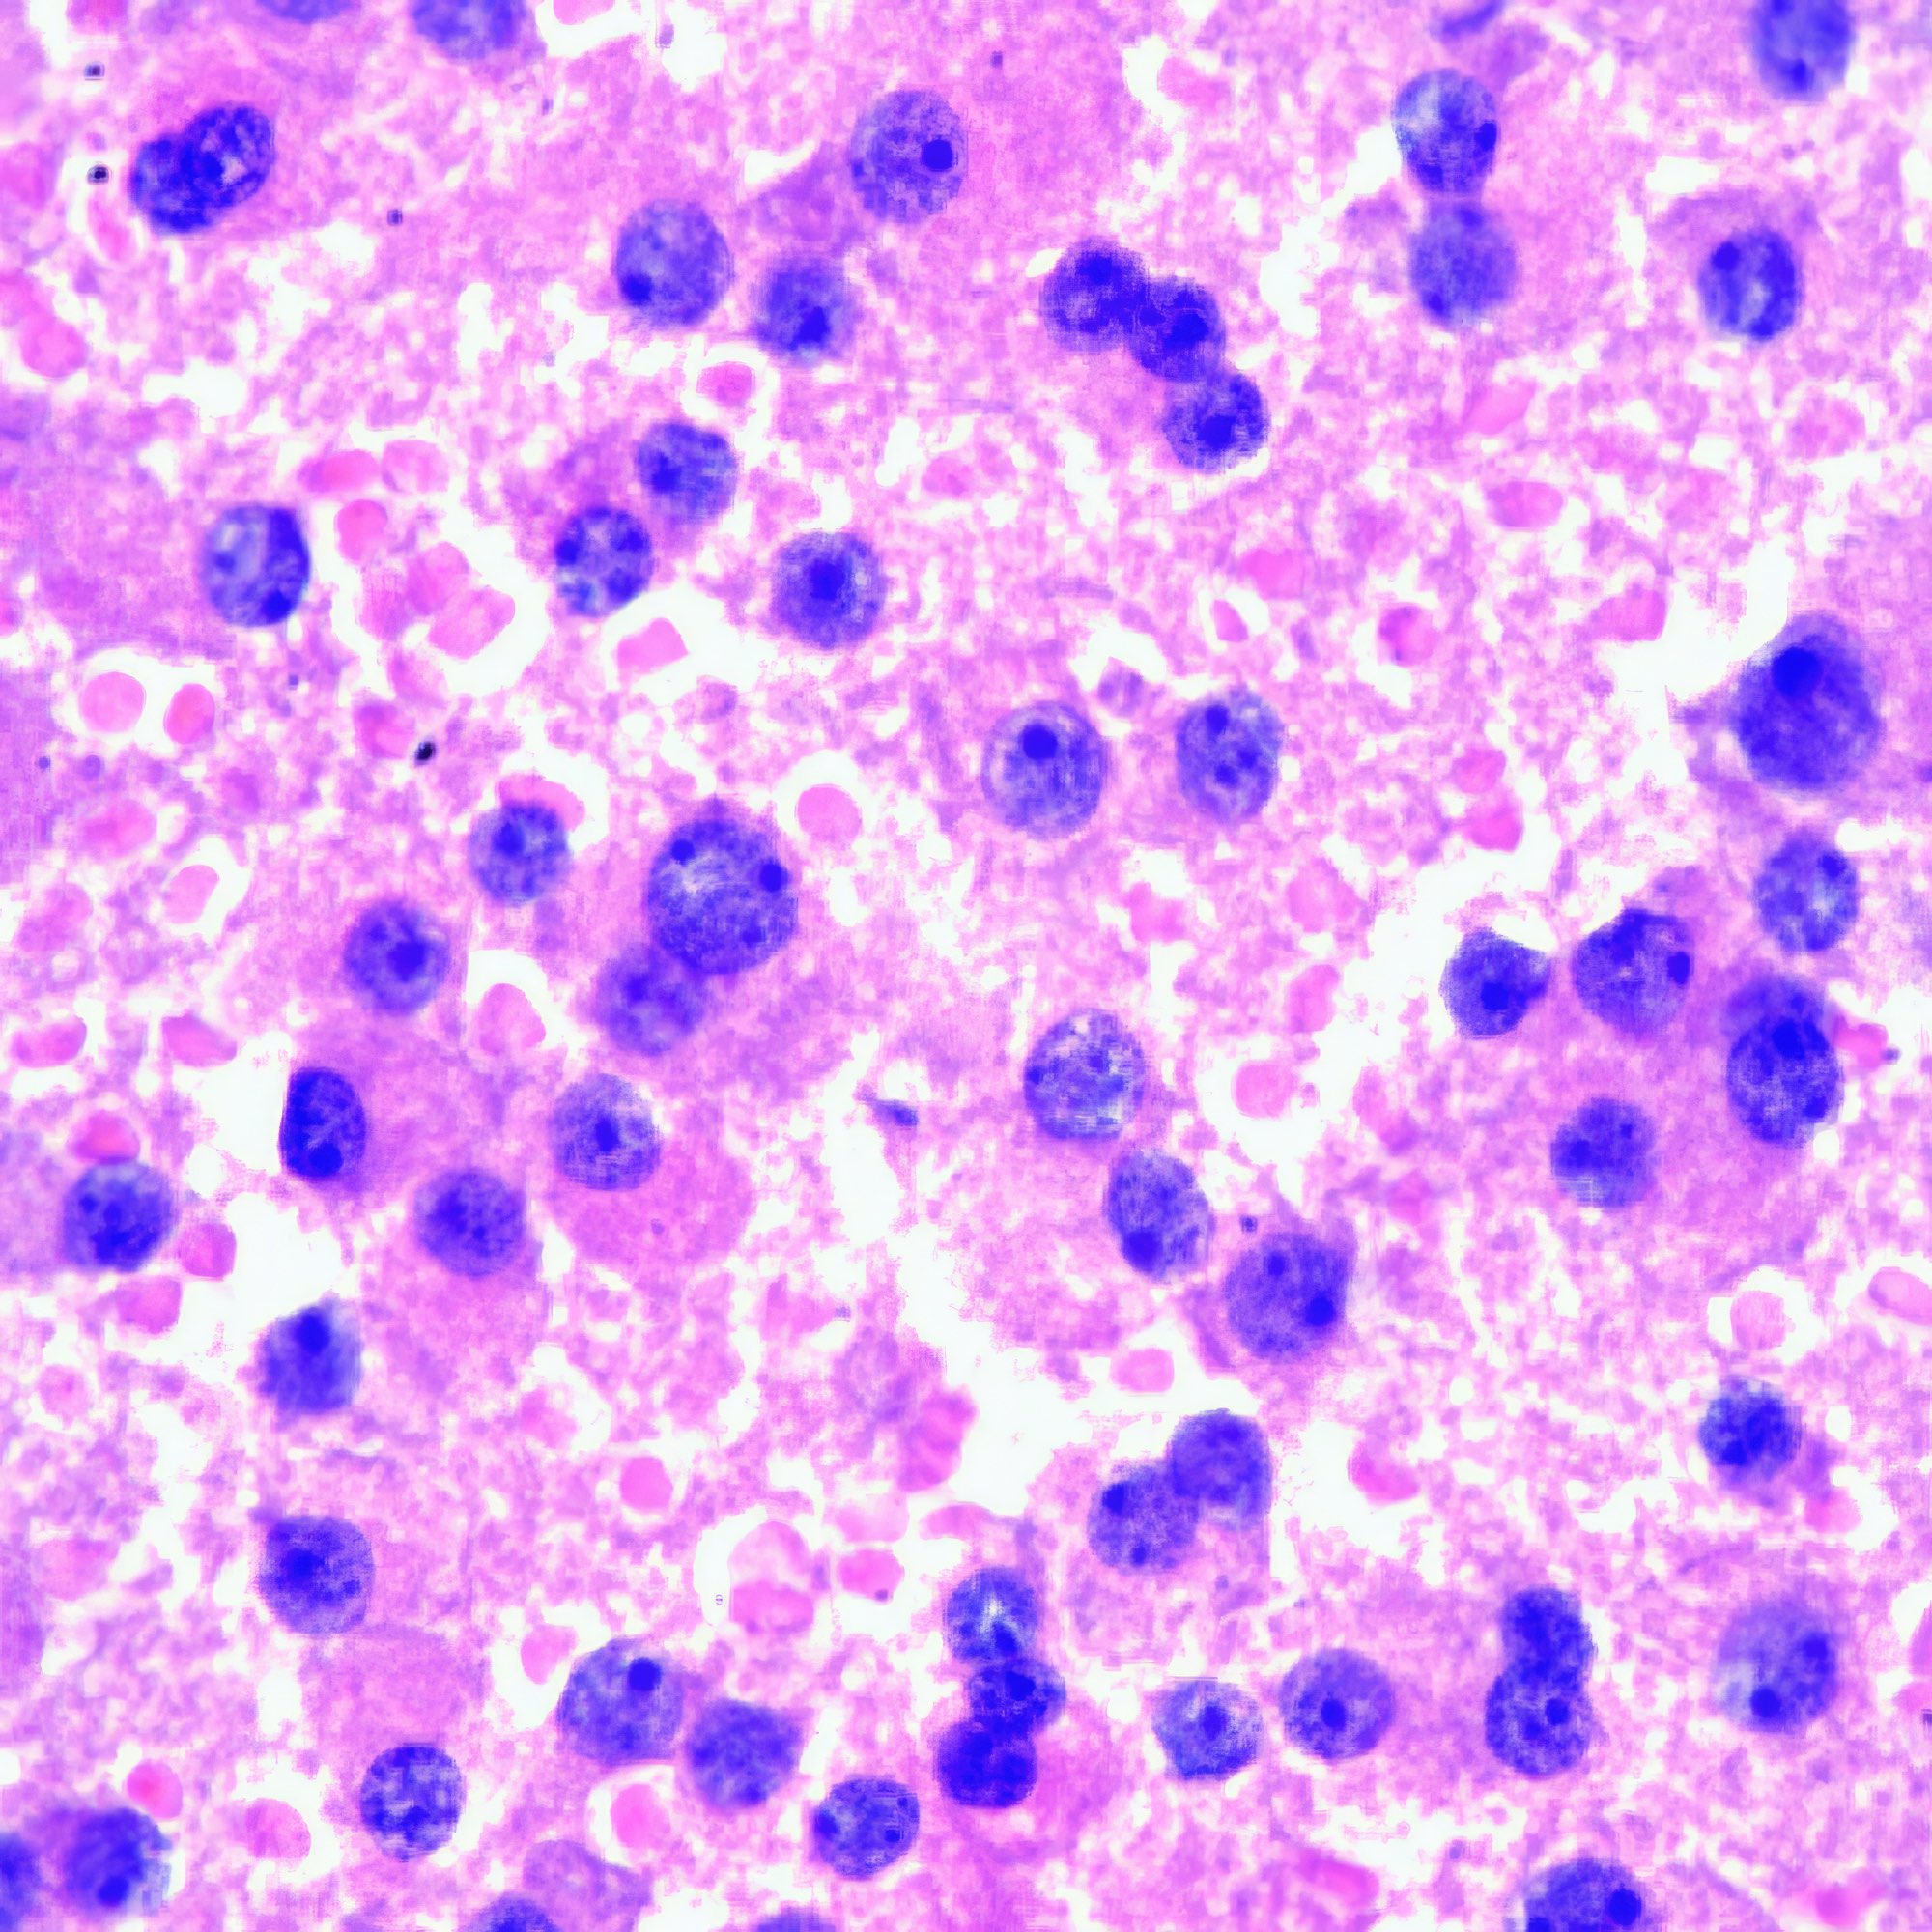

M, 55 Jahre, bemerkte seit 3 Monaten eine zunehmende inguinale Lymphknotenschwellung, der größte 3 x 4 cm messend, davon Feinnadelaspiration (FNA). Abbildung 1 bis 4: Verschiedene Areale des zytologischen Ausstrichs. Orig. 63x

Die Bilder zeigen hochatypische Zellen. Deren überwiegend runde, teils auch ovalen Kerne variieren erheblich in ihrer Größe, sind deutlich grob strukturiert und enthalten meist ein oder mehrere prominente Nukleolen bzw. Chromozentren. Das Zytoplasma erscheint fragil. In jedem Bild finden sich auch Zellen mit pigmentbeladenem Zytoplasma. Der Ausstrichhintergrund enthält Blut und Zelldetritus, ebenfalls vermischt mit Pigmentkörnchen.

Kommentar

Der Patient beobachtete seit einem Jahr am Fuß eine pigmentierte Veränderung, die seit 3 Monaten auf 3 cm Durchmesser zunahm. Die prominente Atypie und die pigmenthaltigen Zellen sowie die ausgedehnte Metastasierung in die inguinalen Lymphknoten sind typisch für das Melanom. Eine Verwechslung des Melanin-Pigments mit Hämosiderin ist wegen der Zellatypie so gut wie ausgeschlossen. – Amelanotische Melanome zeigen oft eine weniger ausgeprägte Kernatypie und sind eher mit einem anderen Tumor zu verwechseln.